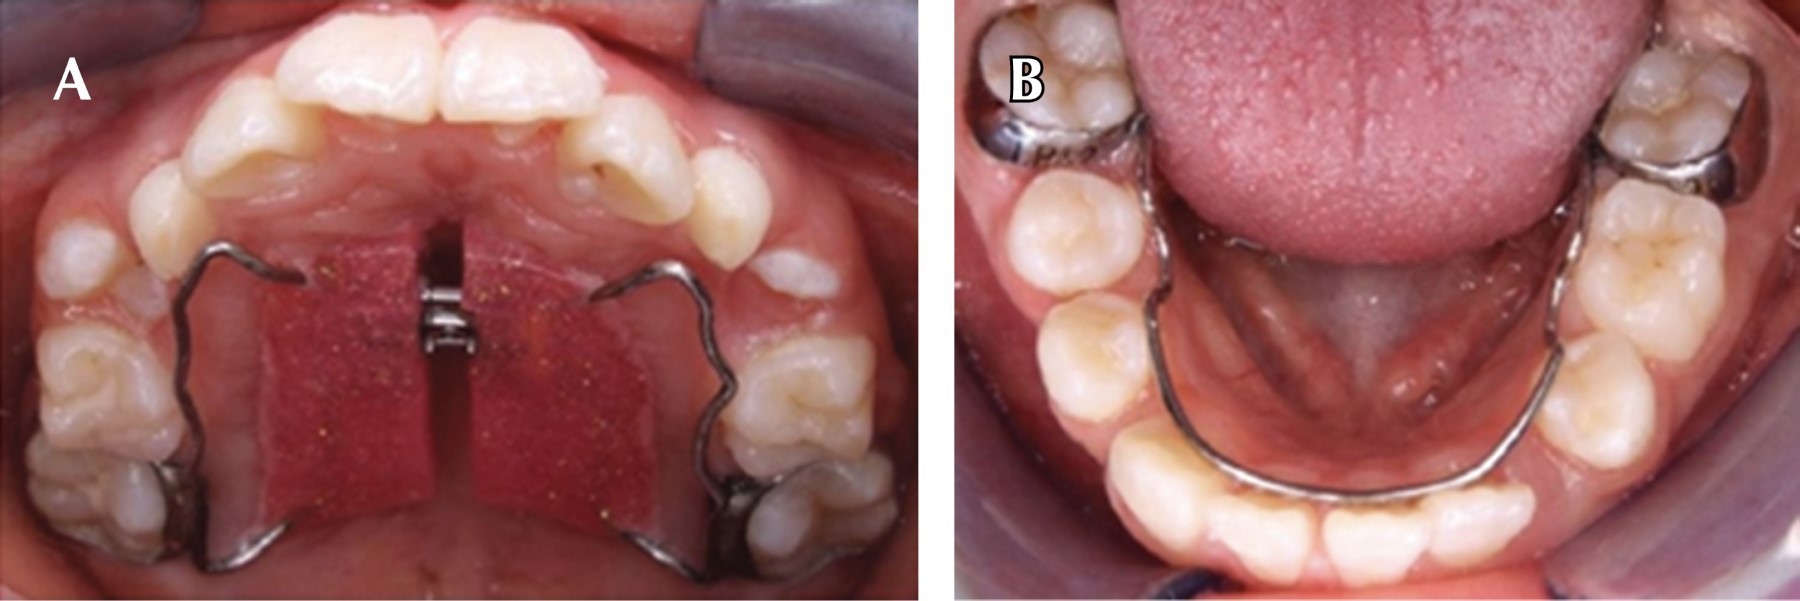

Posterior a la fase preventiva se propuso comenzar con la fase de ortopedia maxilar para mejorar la discrepancia de los maxilares, se tomaron modelos de estudio, fotografías intraorales y extraorales para realizar un diagnóstico. En la primera fase del tratamiento ortodóntico/ortopédico se colocó un botón de Nance en el maxilar superior y un arco lingual en el maxilar inferior para mantener espacio y evitar mesialización de órganos dentarios, ya que radiográficamente se observaron varios dientes con próxima exfoliación, además de estimular el posicionamiento adecuado de la lengua al deglutir. Se dieron las indicaciones de higiene bucal a los padres y a la paciente para valorar su cooperación con el uso de aparatología fija (Figura 5). En la segunda fase (cinco meses después) se realizó el cambio del botón de Nance por un tornillo de expansión tipo Hass debido a la falta de espacio en la arcada superior y por retrusión de órgano dentario 22 (Figura 6), se dieron indicaciones de activación del aparato, una vuelta por semana (0.25 mm) y se continuó con citas mensuales para control del tratamiento.

Figura 5

Figura 6